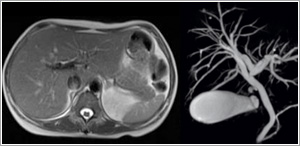

Body MRI

With the availability of fast breath-hold techniques, MRI is now a powerful tool for evaluating diseases of the abdomen and pelvis. As an alternative to ERCP and transhepatic cholangiography, MRCP (MR Cholangiopancreatography) can be performed to non-invasively evaluate the biliary and pancreatic ducts.